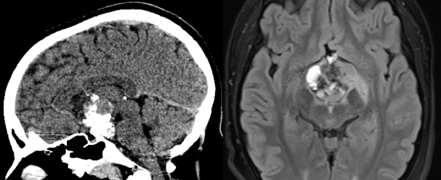

视力模糊、剧烈头痛,14岁的小K从未想过会查出颅咽管瘤。肿瘤位于视交叉后方,而且出现明显的钙化,这也是颅咽管瘤的显著特征。

小K父母找到INC另一位儿童神经外科大咖鲁特卡教授。教授先进行VP分流术缓解脑积水。鲁特卡教授认还通过内镜经鼻入路为小K手术,不开颅顺利全切了肿瘤。

术后,小K的视力得到改善。这是小K的第一次手术,全切是良好预后的基础,他至今未复发。